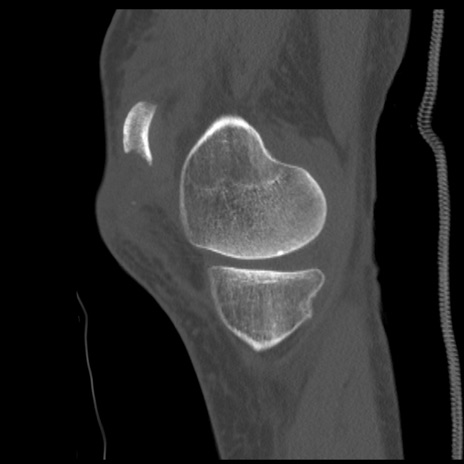

症例28 右膝関節CT(矢状断像)

右膝関節CT